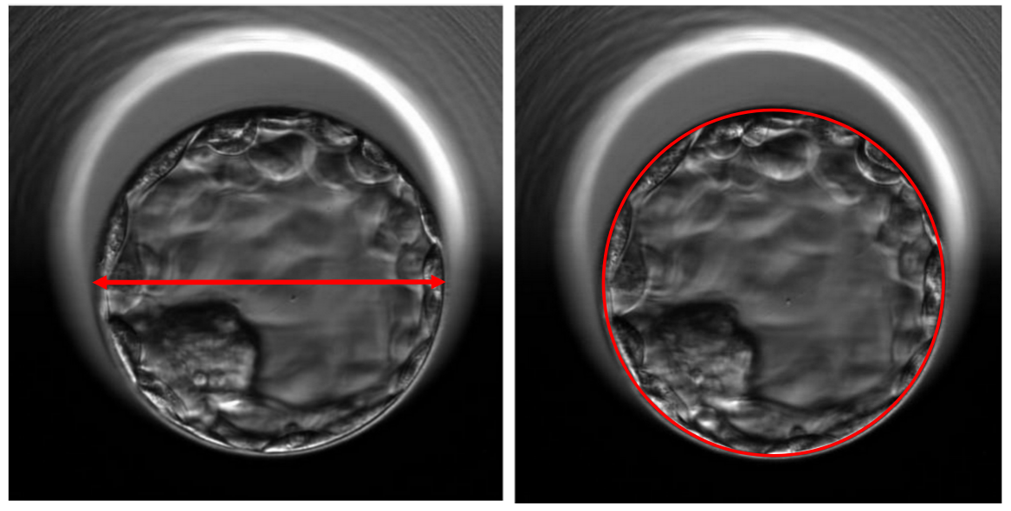

Nghiên cứu này có thiết kế hồi cứu được thực hiện trên 664 chu kỳ IVF/ICSI, sử dụng noãn tự thân và thực hiện chuyển đơn phôi chọn lọc (chuyển phôi tươi) vào ngày 5 (khoảng 112-118 giờ sau thụ tinh). Nghiên cứu viên đã sử dụng phần mềm đi kèm tủ timelapse để đo kích thước đường kính của phôi, đường kính tối đa được xác định bằng cách thực hiện đo bốn lần trên cùng một mặt phẳng quan sát (không tính màng ZP). Bốn mươi bốn phôi nang bị loại khỏi nghiên cứu do lệch khỏi khu vực quan sát của tủ. Những đo đạc này được thực hiện trước khi chuyển phôi và được sử dụng khi phân tích với tỷ lệ thai lâm sàng.

Đối với những phụ nữ có thai lâm sàng, đường kính của phôi nang được chuyển lớn hơn đáng kể so với nhóm không có thai (kích thước trung bình 184 µm (125-239) so với 160 µm (120-230)).

Phân tích hồi quy đơn biến cho thấy tỷ lệ thai lâm sàng tăng khi đường kính phôi nang tăng (OR=1,026, KTC 95% 1,019-1,033, P< 0,01). Phân tích hồi quy cho thấy với mỗi µm đường kính tăng lên, tỷ lệ thai lâm sàng tăng 2,6%.

Tương tự, diện tích phôi nang ở những phụ nữ có thai lâm sàng cao hơn đáng kể so với nhóm không có thai (26,099 µm2 (12,101-45,280) so với 22,251 µm2 (10,992-37,931).

Phân tích hồi quy đơn biến diện tích phôi cho thấy tỷ lệ thai lâm sàng tăng khi diện tích phôi nang tăng (OR=1,00008, KTC 95% 1,00006-1,00011, P< 0,01). Với mỗi µm2 diện tích phôi tăng lên thì tỷ lệ thai tăng 0,008%.